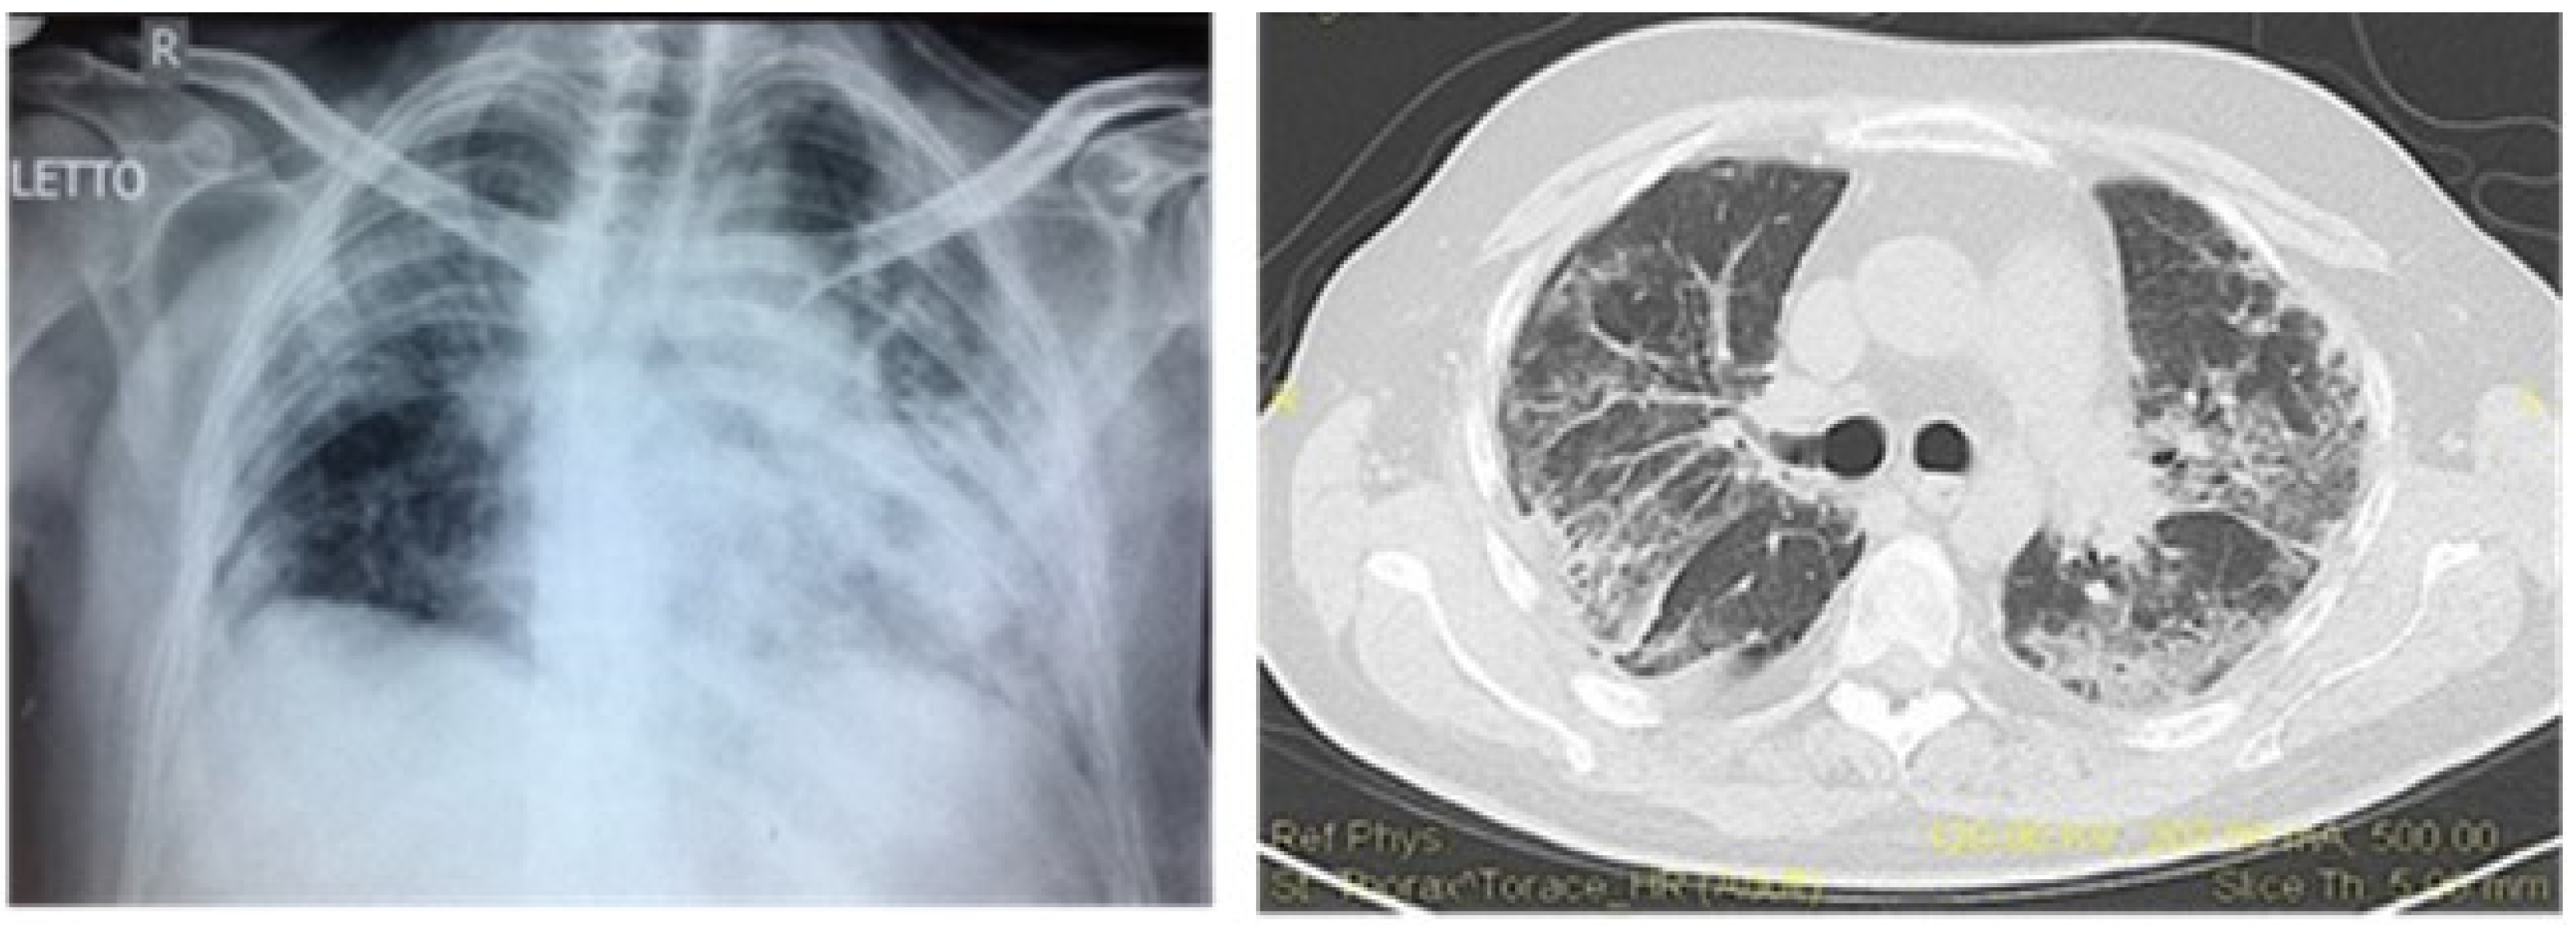

9. Pulmonary Vasculitis

- Nasser, M.; Cottin, V. Alveolar Hemorrhage in Vasculitis (Primary and Secondary). Semin. Respir. Crit. Care Med. 2018, 39, 482–493. [Google Scholar] [CrossRef]

- Wang, C.R.; Liu, M.F.; Weng, C.T.; Lin, W.C.; Li, W.T.; Tsai, H.W. Systemic lupus erythematosus-associated diffuse alveolar haemorrhage: A single-centre experience in Han Chinese patients. Scand. J. Rheumatol. 2018, 47, 392–399. [Google Scholar] [CrossRef]

- Schwab, E.P.; Schumacher, H.R., Jr.; Freundlich, B.; Callegari, P.E. Pulmonary alveolar hemorrhage in systemic lupus erythematosus. Semin. Arthritis Rheum. 1993, 23, 8–15. [Google Scholar] [CrossRef]